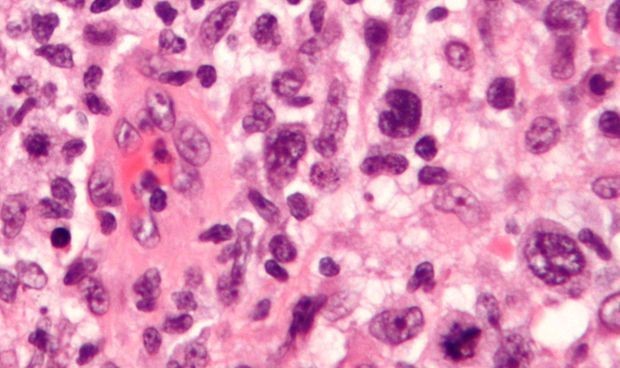

Posteriormente, mediante técnicas de diagnóstico (empleadas no sólo en la asistencia médica, sino también en investigación), como son los estudios inmunohistoquímicos, el grupo de investigación concluyó que todos los tumores analizados eran del tipo de células B centro germinal. Además, en las muestras de ratón se han detectado mutaciones presentes en las muestras humanas de linfomas difusos de células B grandes.